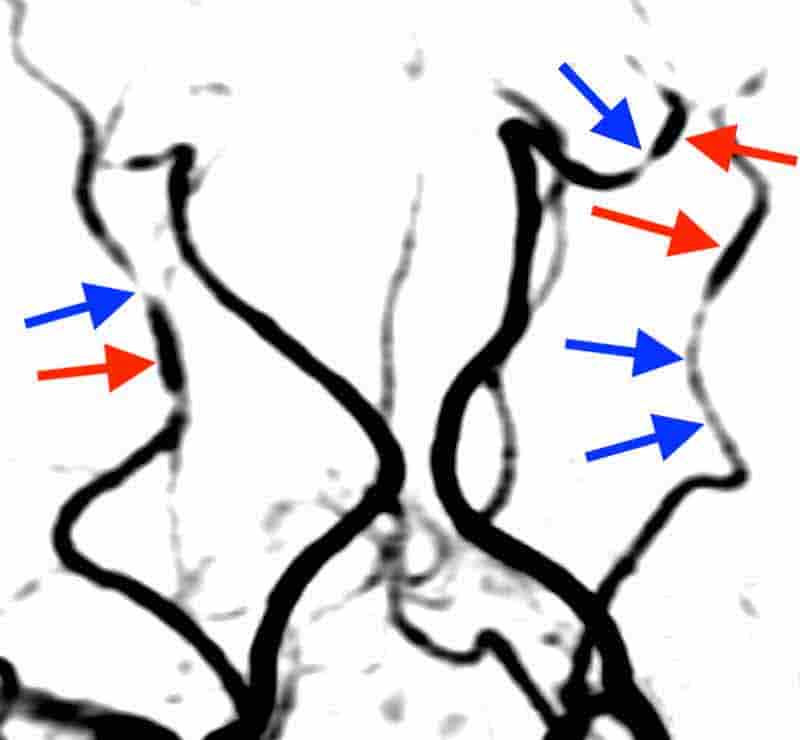

MRA検査では、

脳の血管が、まるでネックレスのような形に変化していました。

MRA検査を行いました。

脳動脈のいたる所に、収縮(青い矢印)と拡張(赤い矢印)を認めました。